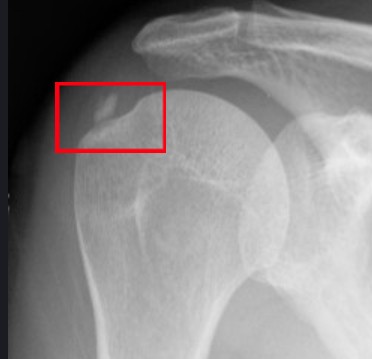

어깨 부위와 오른쪽 팔 상단 쪽을 엑스레이 촬영을 하고 그 부분을 함께 보여주셨습니다. 엑스레이에는 어깨 부위에 뿌옇게 뭔가 보였는데 그게 석회라고 하셨습니다. 석회 덩어리가 커져서 어깨를 회전할 때마다 근육을 찔러 통증을 유발한다고 말씀하셨습니다.

일반적으로 뼈에서는 석회가 원래 나오고 나왔던 석회가 다시 뼈로 흡수되는 과정이 반복되는데 그 과정 중에 석회가 남고 흡수가 잘 안 될 경우 석회가 뭉쳐서 통증을 유발한다고 합니다. 사실 이렇게 뭉친 석회는 쉽게 흡수가 이루어지지 않지만 결국 아주 오랜 시간이 지나면 자연 흡수도 가능하다고 합니다. 다만 그동안 발생하는 통증이 문제인 것입니다.

첫 엑스레이에서 덩어리로 보이던 석회는 작은 조각으로 바뀌어 있었습니다. 의사 선생님께서는 여기서 체외 충격파를 해도 더 이상 사이즈가 줄어들 것 같지도 않고 조각이 충분히 작아졌으니까 이대로 자연스럽게 뼈로 흡수될 것이라고 알려 주셨습니다.